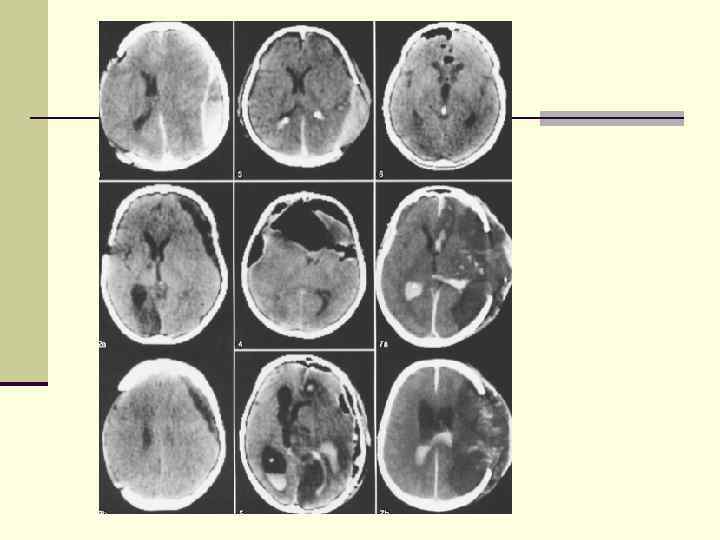

Множественные контузионные очаги динамика (через 2 мес) Множественные контузионные очаги динамика (через 2 мес)